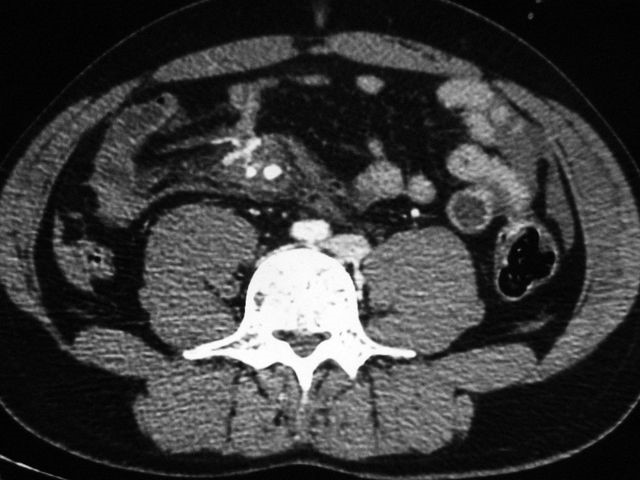

Компьютерная томография

Этот метод диагностики заключается в исследовании желудочно-кишечного тракта с помощью томографа, который использует рентгеновские лучи. Процедура проходит следующим образом: пациент располагается на столе томографа, где его облучают рентгеновскими импульсами. Чем плотнее ткань, тем меньше рентгеновских лучей проходит через нее, что позволяет выявить патологические изменения в органах, такие как опухоли, уплотнения и эрозии. Темные и четкие участки на снимках могут указывать на наличие полипов, в то время как светлые области свидетельствуют об отсутствии новообразований.

Принцип работы томографа заключается в его вращении, которое позволяет делать снимки срезов тканей и выводить результаты на экран. Однако у этого метода есть значительные недостатки: он не позволяет обнаружить мелкие патологии, а также перед диагностикой требуется введение трубки для перфораций.

Данный метод противопоказан для беременных женщин и пациентов с избыточным весом. Кроме того, стоит отметить, что исследование связано с повышенным уровнем рентгеновского облучения.

Компьютерная томография не является высокоинформативным методом и используется преимущественно для предварительной диагностики. Если в ходе исследования обнаруживаются какие-либо патологии, пациенту могут быть назначены эндоскопическое или капсульное гастроскопирование для более детального анализа.